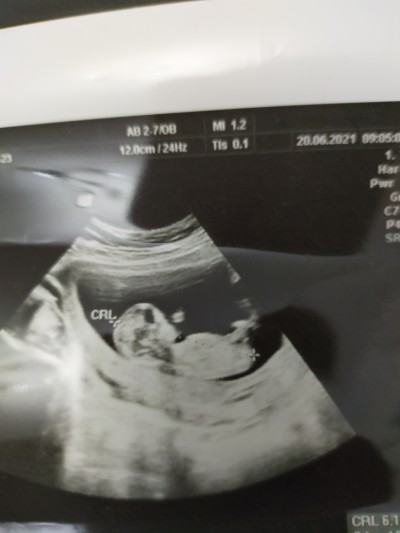

Hamiş anneler bugün cinsiyet öğrenmeye gidicez çok heyecanlıyım yüklediğim fotoğrafa sadece tahmin istiyorum lütfen kırıcı olmayalım heyecanımı bastırmak istiyorum tabiki her iki şekilde de evlat bizim evladımız her şeyin başı sağlık tahminleriniz nedir acaba

İyi akşamlar arkadaşım hastaneden döndüm doktor yüzde 70 erkek dedi  çok mutluyum tahmininde net erkek demiştin

Ya hadi gözün aydın canım. Orada bir pipi gördüm çünkü :D kordonun altında :D

Gördüğüm kadarıyla, iskelet yapısı net belli olan bebekler erkek, çok da belli olmayanlar kız oluyor. Benim oğlumla kızımın da öyleydi. Çevremde de nette de hep öyle denk geldim. Ordan yola çıkarak erkek diyorum. Ama tabi ki gaybı bilen yalnız Allahtır, her şeye açık olmak lazım :)

Hmmm yani çıkıntılı olduğu için anladınız umarım öyle olur çünkü önce sağlık tabiki ama yüreğimden erkek geçiriyorum Allah nasip etsin inşaallah iki kızım var bu da erkek olur inşaallah

Ordaki pipiyi bir tek ben görmüş olamam

İşte sorun orda kuzum onun pipi veya kordon bağı olup olmadığı tartışmaya açık konu hale geldi

Evet canım doktor %70 erkek bebek dedi